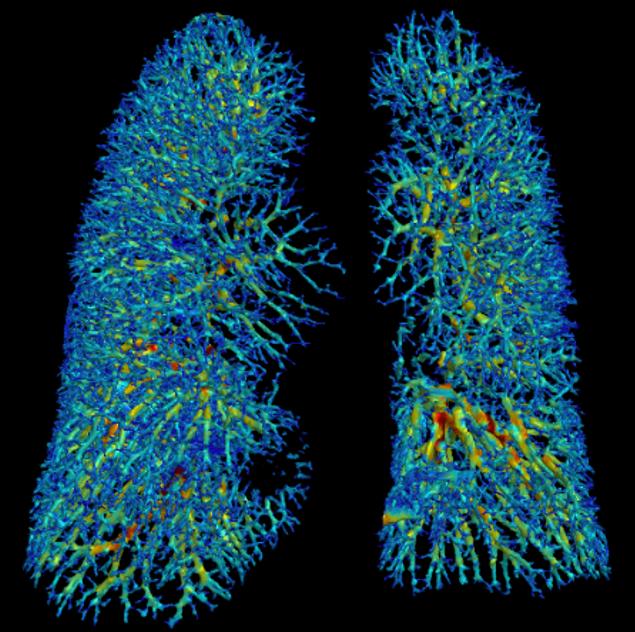

The PAIRR (Pulmonary Artificial Intelligence and Radiomics Research) Laboratory is a research unit of the Department of Radiology at UMass Memorial Medical Center and UMass Chan Medical School. Its mission is to develop, test, and implement innovative technology based on Artificial intelligence (AI) and Radiomics in the field of respiratory imaging.

The core research projects of the PAIRR Laboratory are based on accuracy and efficiency testing of novel AI and radiomics technologies. Additional research is focused on evaluating novel approaches to using these technologies, for example by combining or blending algorithms. Efficiency testing revolves around clinical algorithm implementation and the associated impact on work-flow and costs. Finally, a branch of research aims to develop and test mechanisms and metrics to quantify the “added-value” of novel technology to the clinical radiology workplace, and to analyze the increasing complexity of information generated by this technology.